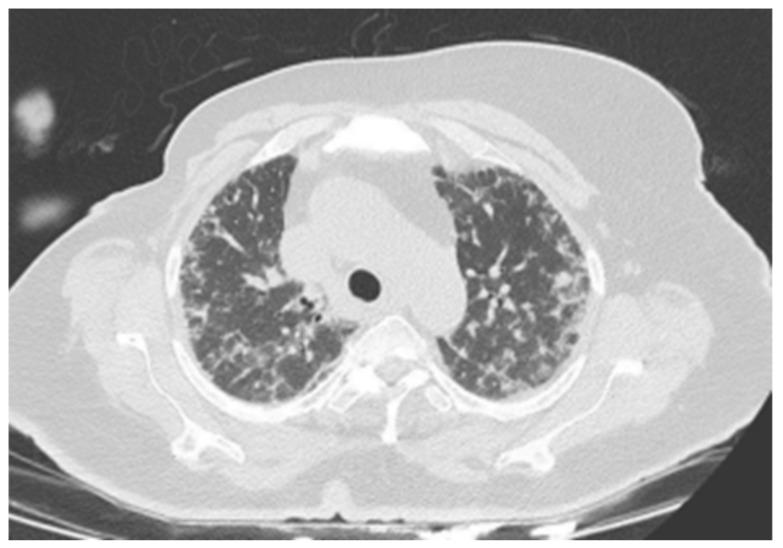

CDK4/6 inhibitors (CDK4/6i) have revolutionized the treatment of hormone receptor-positive HER2 negative (HR(+)/HER2(-)) breast cancer. Despite their efficacy, interstitial lung disease (ILD) remains a rare but potentially fatal adverse effect. This study aims to evaluate the incidence and clinical characteristics of ILD associated with CDK4/6 inhibitors in breast cancer patients in Turkey. : A retrospective multicenter analysis included 464 breast cancer patients treated with CDK4/6 inhibitors between January 2017 and April 2024. Patients receiving ribociclib or palbociclib were evaluated for the development of ILD. Radiological assessments were performed to confirm ILD and exclude other conditions. Clinical characteristics, treatment regimens, and outcomes were analyzed. : ILD was identified in 10 patients (2.1%). The average age of the affected patients was 62.5 ± 9.85 years. Hypersensitivity pneumonitis and nonspecific interstitial pneumonia (NSIP) were the most common radiological patterns. Palbociclib was implicated in six cases, while ribociclib was associated with four cases. Grade 3 pulmonary toxicity was observed in eight patients, and Grade 4 toxicity in two patients. One patient who was on palbociclib died due to ILD. No significant correlation was found between ILD and age, smoking status, lung metastases, or prior thoracic radiotherapy. : The incidence of CDK4/6 inhibitor-associated ILD in Turkish breast cancer patients appears higher than previously reported in clinical trials. More robust, long-term studies are necessary to identify potential risk factors and mitigate ILD-related mortality.

细胞周期蛋白依赖性激酶4/6抑制剂(CDK4/6i)彻底改变了激素受体阳性、人表皮生长因子受体2阴性(HR(+)/HER2(-))乳腺癌的治疗方式。尽管其疗效显著,但间质性肺疾病(ILD)仍然是一种罕见但可能致命的不良反应。本研究旨在评估土耳其乳腺癌患者中与CDK4/6抑制剂相关的ILD的发生率和临床特征。:一项回顾性多中心分析纳入了2017年1月至2024年4月期间接受CDK4/6抑制剂治疗的464例乳腺癌患者。对接受瑞博西尼或哌柏西利治疗的患者进行ILD发生情况评估。进行影像学评估以确诊ILD并排除其他疾病。分析临床特征、治疗方案和结局。:10例患者(2.1%)被确诊为ILD。受影响患者的平均年龄为62.5±9.85岁。过敏性肺炎和非特异性间质性肺炎(NSIP)是最常见的影像学表现。哌柏西利涉及6例,而瑞博西尼与4例相关。8例患者出现3级肺部毒性,2例患者出现4级毒性。1例接受哌柏西利治疗的患者因ILD死亡。未发现ILD与年龄、吸烟状况、肺转移或既往胸部放疗之间存在显著相关性。:土耳其乳腺癌患者中与CDK4/6抑制剂相关的ILD发生率似乎高于先前临床试验报告的发生率。需要更有力的长期研究来确定潜在风险因素并降低与ILD相关的死亡率。